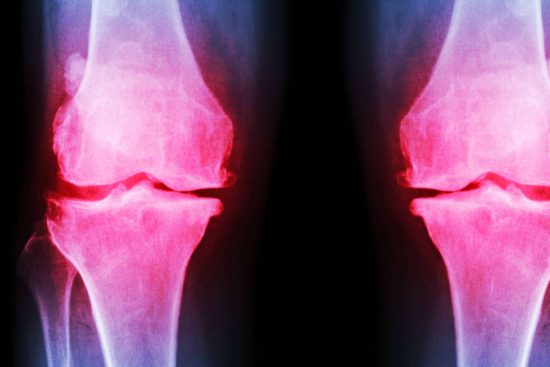

La fisioterapia es una herramienta de gran importancia para los pacientes que han sufrido una lesión, traumatismos o un accidente cerebrovascular, así como para quienes padezcan dolores crónicos, efectos secundarios de tratamientos médicos y distintos tipos de disfunciones. Por esta razón, mediante los métodos novedosos, sesiones y técnicas punteras aplicadas es posible recuperar, rehabilitar y mejorar las capacidades para la vida diaria, a la vez que previene enfermedades.

Para determinar con exactitud cuál es la patología que afecta al paciente y plantear los pasos a seguir para su tratamiento, es imprescindible acudir a una clínica de fisioterapia especializada que cuente con todos los recursos necesarios para una atención profesional. Este es el caso de Clínica Azorín, un establecimiento de fisioterapia especializada en Albacete que aúna los recursos humanos más cualificados con tecnología avanzada para la evaluación, el diagnóstico y la corrección de distintas problemáticas físicas.